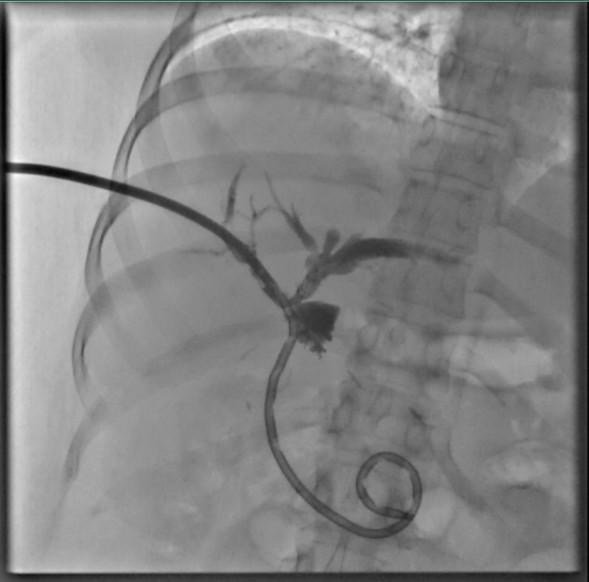

La institución dio a conocer que la colangioscopía percutánea surge como la “llave maestra” cuando los métodos convencionales fallan, en pacientes donde la anatomía ha sido alterada por cirugías previas o donde los endoscopios estándar no pueden ingresar, esta técnica mínimamente invasiva abre una ruta directa al sistema biliar.

A diferencia de las imágenes granuladas de las técnicas tradicionales, este abordaje ofrece una visión nítida y en tiempo real, permitiendo a los médicos actuar con la precisión de un relojero dentro del cuerpo humano.

El impacto real de esta tecnología se refleja en los casos de éxito atendidos en el ISSSTE durante esta jornada inaugural, el primero una joven de 32 años, quien ya arrastraba antecedentes de cirugías biliares y padecía cálculos alojados peligrosamente dentro del hígado, fue intervenida mediante litotricia electrohidráulica.

A través de potentes ondas de choque dirigidas, los médicos pulverizaron las piedras sin necesidad de realizar incisiones mayores, eliminando riesgos postoperatorios críticos.

El segundo caso, un hombre de 48 años, presentaba un estrechamiento del conducto biliar (estenosis) de causa desconocida que los estudios de imagen comunes no lograban descifrar.

Con la colangioscopía, el equipo médico pudo observar la lesión de frente y realizó biopsias dirigidas, garantizando un diagnóstico certero para un tratamiento inmediato.